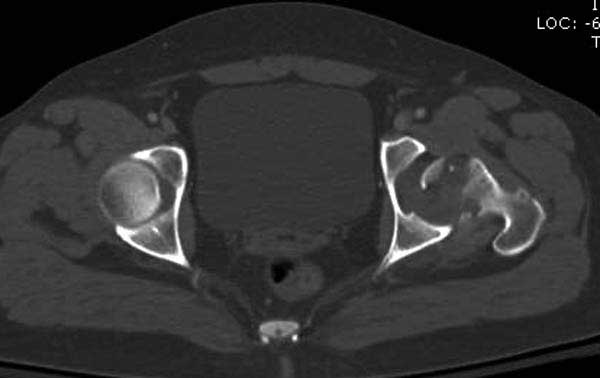

В диагноз еще необходимо внести закрытую (?) ротационно-нестабильную травму таза с переломами лонных седалищных костей, боковой массы крестца справа.

Перелом позвоночника и боковую компрессию таза отнесли к стабильным переломам и не стали форсировать события до лучших времен...